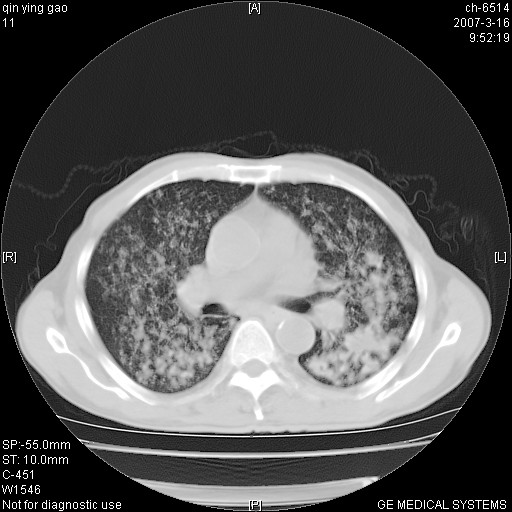

男,64岁.乏力2个月,畏寒、发热1月余。体重下降。血沉加快,白细胞不高。

双肺可见大小不等结节状密度增高影,密度不均,分布不均(双肺上叶为著),亚急性血行播散性肺结核.

(本例特征:以大小不等结节为主,主要分布在双上肺,并部分病灶融合成较大结节,期间搀杂诸多细小结节。从病灶特点与分布形式分析,更趋向于感染。)

以双肺上叶为主的弥漫型斑片状密度增高影,边界欠清晰,其中伴有钙化灶,病人有发热史,首先考虑感染性病变:1特殊类型感染,2结核。建议治疗后随诊复查,除外肺泡癌

两中上肺见有广泛分布大小不一的结节灶及斑片状影,部分融合,双下肺未见异常密度影,纵隔无明显肿大淋巴结,血沉加快,白细胞不高,首先考虑结核。 建议结合ppd检查或痰培养排除其他非特异性炎症。

中上肺野密布棉团状影,以胸膜下区为界,边缘模糊,可能是小叶或腺泡渗出及实变。全肺野弥漫分布网线样影及细小粟粒样影,可能是细支气管炎及间质内炎症。综合分析应首先考虑气道播散性感染,而肺内多处斑点性钙化,强烈提示陈旧结核复发并支气管播散。建议详细讯问病史

病变以两肺上野为著,部分病灶有钙化,纵隔窗显示病灶有新老不一,这个首先和结核脱不了干系,还有部分病灶有融洽的倾向,肿瘤也不能完全排出